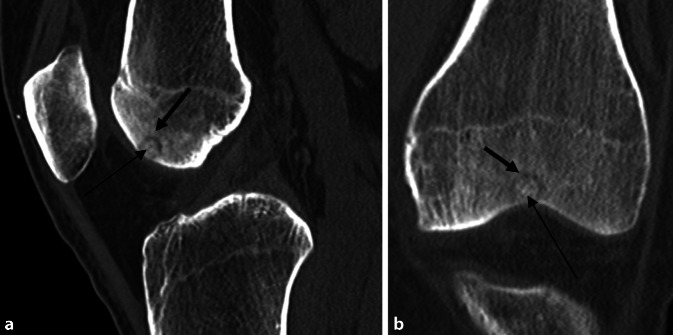

Die CT-Diagnostik bestätigte den Befund einer subchondralen, epiphysären Läsion interkondylär, vereinbar mit einem Osteoidosteom bei hyodensem Nidus mit hyperdenser Kalzifizierung (Abb. 2). Das initial durchgeführte Röntgenbild (Abb. 4) zeigt indes keine wegweisenden Auffälligkeiten.

Bei progredienten MRT-Befunden und der Diagnosesicherung des Osteoidosteoms mittels CT (Abb. 2) wurde die Radiofrequenzablation mit den Kollegen der Radiologie ausführlich diskutiert. Diese war aber aufgrund der Nähe des Nidus zur subchondralen Lamelle und MRT-morphologisch vermutetem Kontakt zum Gelenkknorpel kontraindiziert (Abb. 5).